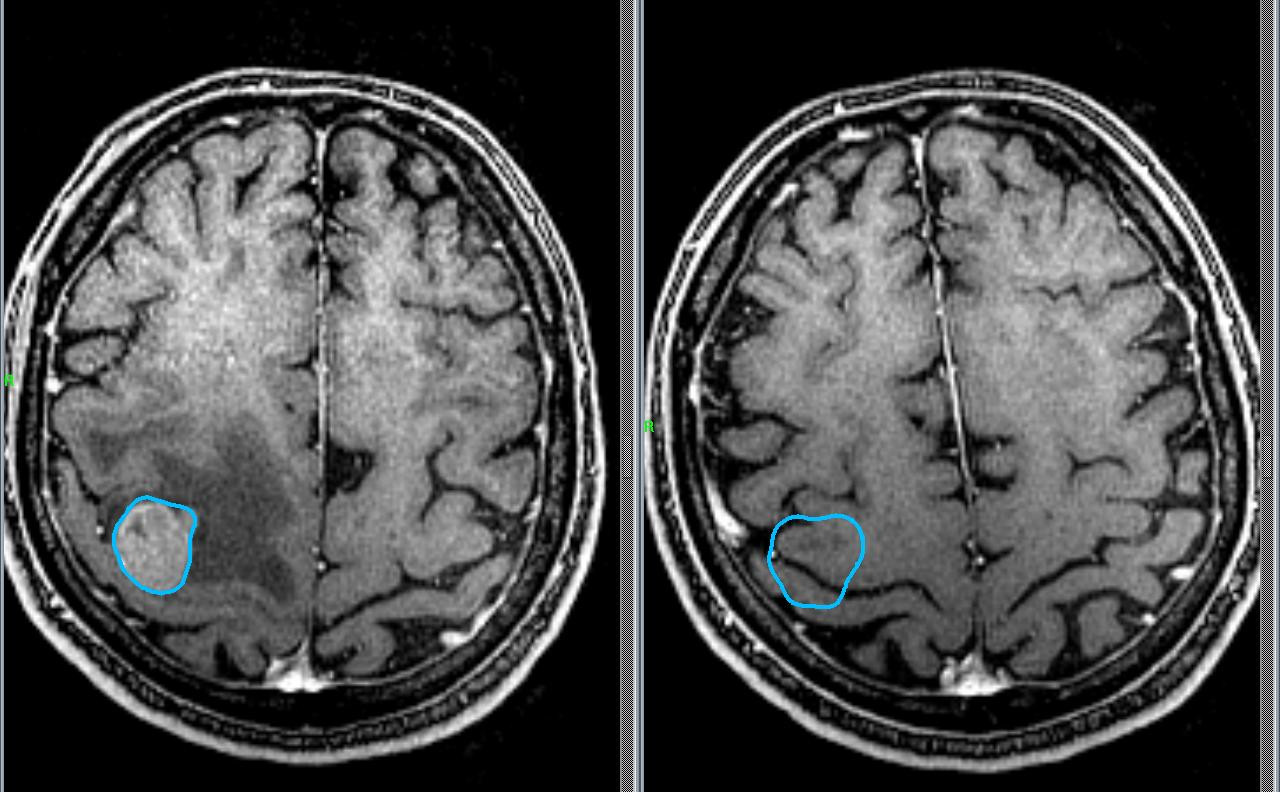

Американские ученые из Онкологического центра им. М.Д.Андерсона при Университете Техаса недавно обнаружили фермент, который помогает злокачественным опухолям головного мозга расти и распространяться, несмотря на то, что окружающая среда будто бы этому не способствует (из-за небольшого количества кислорода и питательных веществ).

Всемирная организация здравоохранения различает более 120 типов опухолей головного мозга. Это довольно распространенное заболевание. Так, например, в США насчитывается свыше 700 тыс. человек с первичной опухолью мозга. Ежегодно почти у 80 тыс. американцев диагностируют рак мозга.

Всем раковым клеткам для того, чтобы расти и распространяться нужно питаться. В этом они схожи со здоровыми клетками. Ни раковые, ни здоровые клетки не могут обойтись без питательных веществ и кислорода. Но некоторые злокачественные опухоли иногда локализуются там, где для них мало пищи.

Ответ на этот вопрос сумели найти американские ученые из Онкологического центра им. М.Д.Андерсона при Университете Техаса. Оказывается, все дело в специальном ферменте ACSS2. Благодаря этому ферменту злокачественная опухоль лучше усваивает ацетат натрия, клеточную соль, которая является хорошим поставщиком углерода при недостатке глюкозы. Для роста и распространения раковых опухолей больше подходит глюкоза, но ее часто в местах воспаления бывает очень мало. Поэтому раковые клетки питаются углеродом, получая его из ацетата натрия.

Ученым уже давно известно про негативную роль ацетата натрия в развитии раковых клеток. Если заблокировать поступление питательных веществ в злокачественную опухоль по этому пути, то это приведет к предотвращению ее роста и смерти раковых клеток. Правда, пока ученые, несмотря на новейшие технологии, так и не научились блокировать этот путь поступления питательных веществ в опухоли.